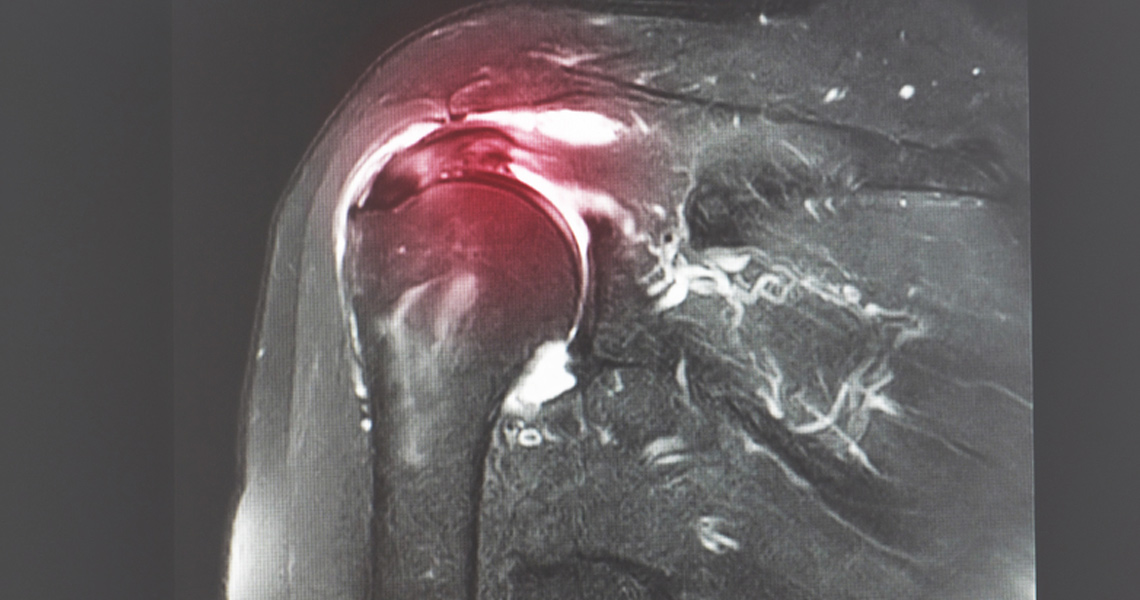

Shoulder arthroscopy is a minimally invasive surgical procedure that allows orthopaedic surgeons to visualise, diagnose, and treat a variety of shoulder conditions through small incisions using a specialised instrument called an arthroscope. This procedure is commonly performed to address issues such as rotator cuff tears, labral tears, shoulder impingement, shoulder instability, and shoulder arthritis. Shoulder arthroscopy offers several advantages over traditional open surgery, including smaller incisions, less tissue damage, faster recovery times, and reduced postoperative pain.

Rotator Cuff Tears: The rotator cuff is a group of muscles and tendons that surround the shoulder joint, providing stability and facilitating movement. Tears in the rotator cuff can occur due to injury, overuse, or degeneration, leading to pain, weakness, and limited mobility. Shoulder arthroscopy is often used to repair or reconstruct the torn rotator cuff tissue, restoring function and preventing further joint damage.

Preoperative Evaluation: Before undergoing shoulder arthroscopy, patients undergo a thorough evaluation, including physical examination, imaging studies (such as X-rays and MRI), and medical history review. This helps our orthopaedic surgeons determine the underlying cause of shoulder pain and develop a personalised treatment plan.